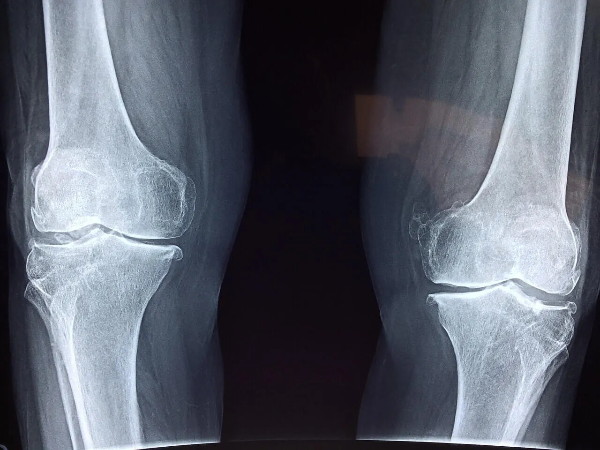

이 균형이 무너지면,

뼈는 조용히

그러나 빠르게 약해집니다.

아프지 않게 진행됩니다.

뼈 밀도가 서서히 줄어들고,

구조가 약해져도

몸은 거의 신호를 보내지 않습니다.